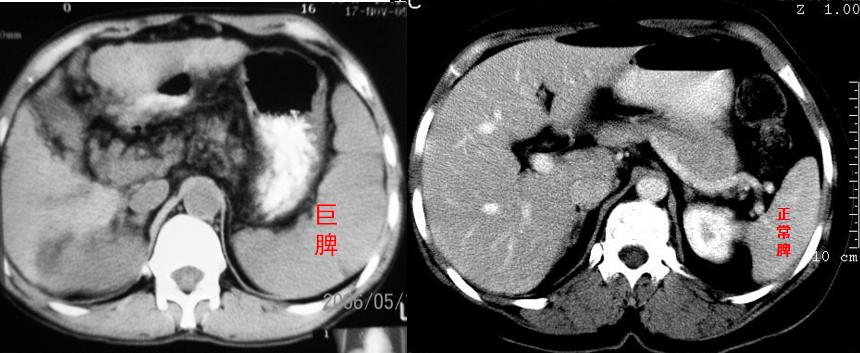

巨脾与正常脾的CT对照

脾脏是人体内的一个器官,与中医所说的“心肝脾肺肾”中的脾并不等同。脾脏的主要功能是清除血液中“老弱病残”的红细胞、白细胞和血小板,维持血液成分的正常稳定。然而,脾脏增大后,清除上述细胞的能力也就“水涨船高”,功能过于强大,就是所谓的“功能亢进”了。